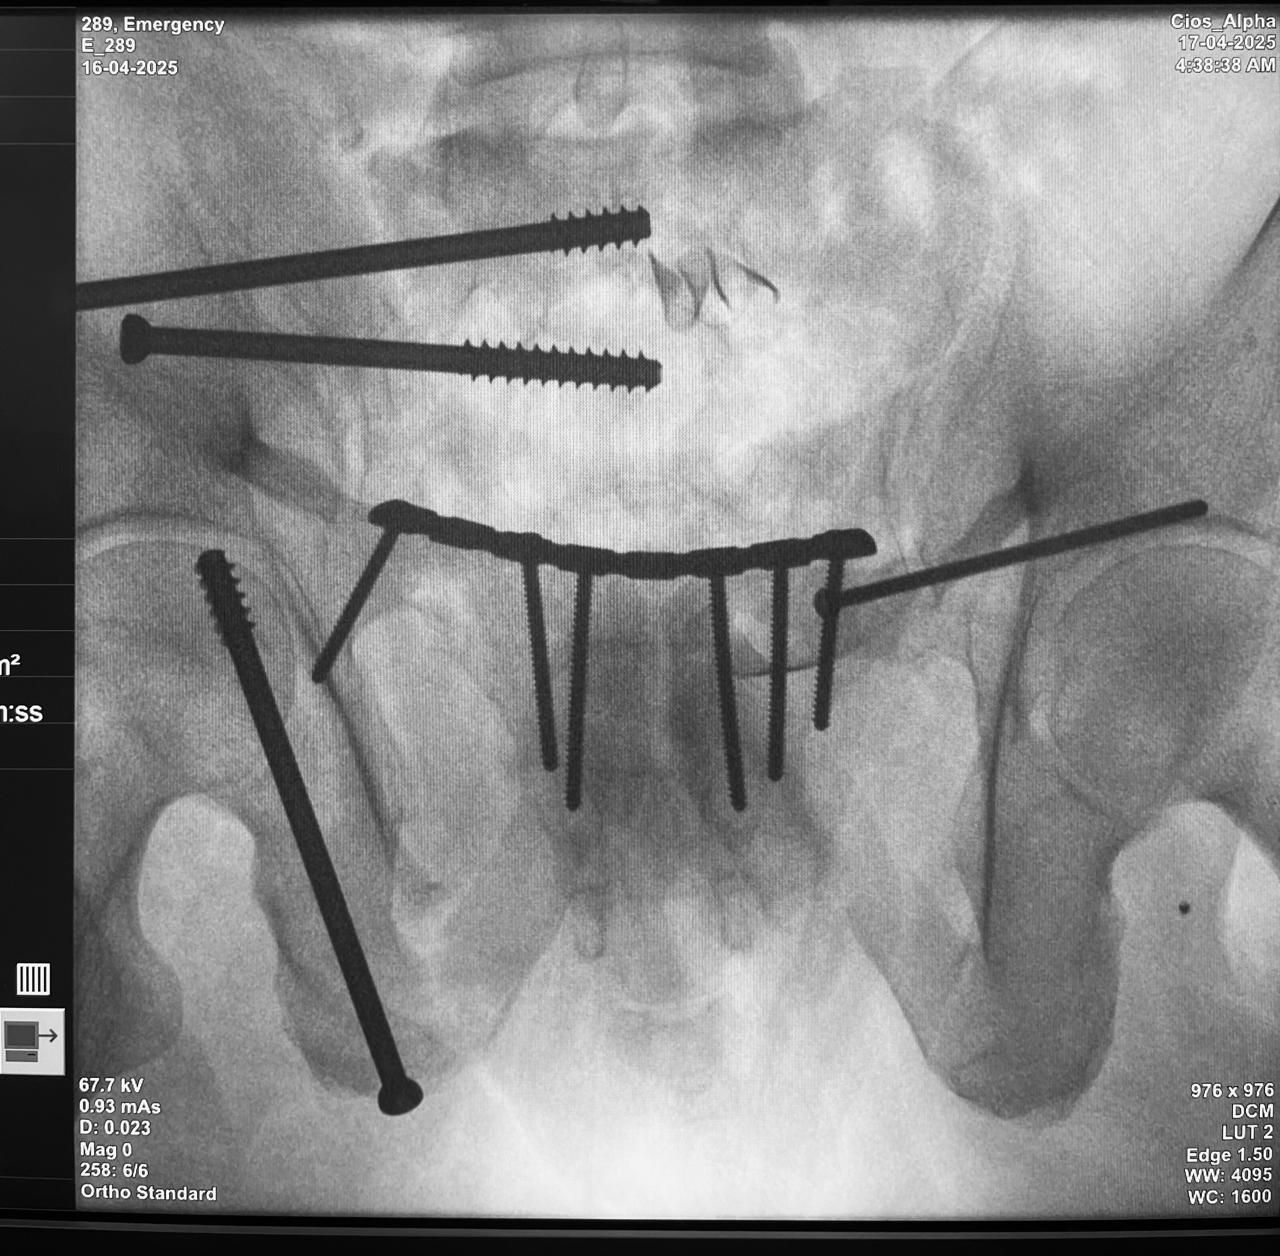

• Trauma de urgencia

• Infecciones óseas y pseudoartrosis